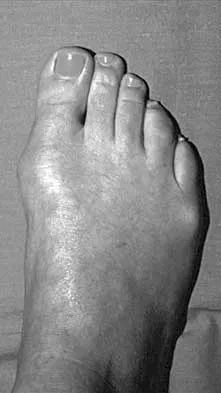

Question 88

A 16-year-old boy has had a painful ingrown nail on his great toe for the past 3 months. When initial management consisting of soaking the foot in Epsom salts and trimming the nail failed to provide relief, his family physician recommended 2 weeks of oral antibiotics. His symptoms persist, and he is now seeking a second opinion. A clinical photograph is shown in Figure 18. Management should now consist of

Explanation